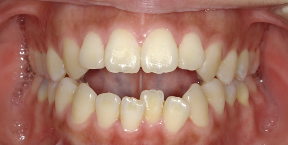

26歳女性のビフォーアフター

| 診断 | 空隙,叢生 |

| 治療方針 | 治療方針:前歯の咬合関係改善と空隙閉鎖を主な目的にて主にIPR(歯と歯の間をわずかに削合してスペースを獲得する方法)を組み込んだ動的矯正治療を行い、空隙、前歯咬合を改善後、保定を行う。臼歯部の咬合関係はプランの都合上維持することとした |

| 治療費 ※ | 69万8千円(診断、型取り、矯正中のメンテナンス、保定装置を含む料金) |

| 治療期間 | 1年8か月 |

| リスク | 1日20時間以上マウスピースを使用できない場合、歯が動かなかったり、想定しない誤差により不完全に終わる可能性がある。装着時や食事時に痛みを伴う。歯肉退縮や虫歯になるおそれがある。また、指導通りに装着できていない場合や適切なブラッシングが出来ていないとそのリスクが高くなる。歯根が短くなることがある。ごくまれに歯の神経が損傷してしまうことがある。過去にぶつけたり深い虫歯治療をしたことがあるとそのリスクはやや高くなる。矯正後には保定装置が必要。適切な使用ができない場合、後戻りの原因となる。将来的に歯並びが動いて再矯正が必要な場合がある。舌癖(舌で歯を押し出す癖)親知らずが正常に生えていない場合、その可能性がやや高くなる。 |